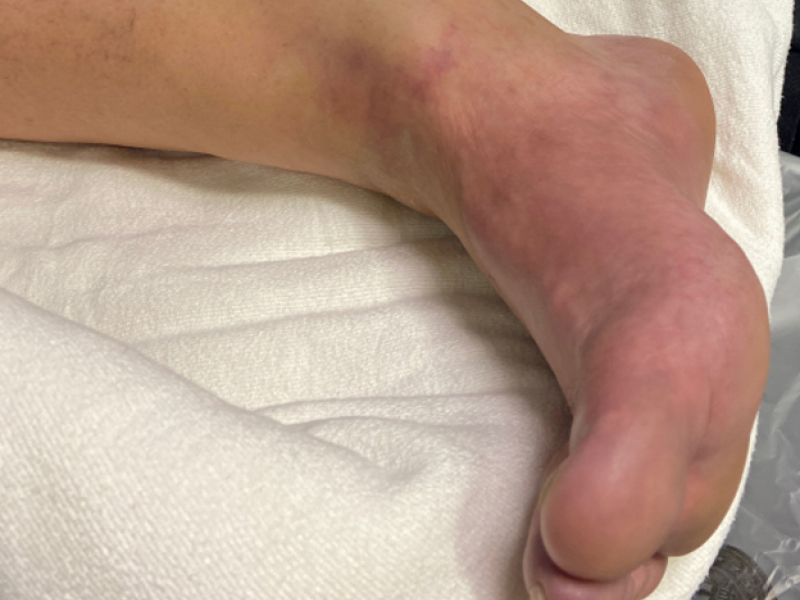

Back to Basics: Ankle Injury By: Charlie Ingram CC: Ankle